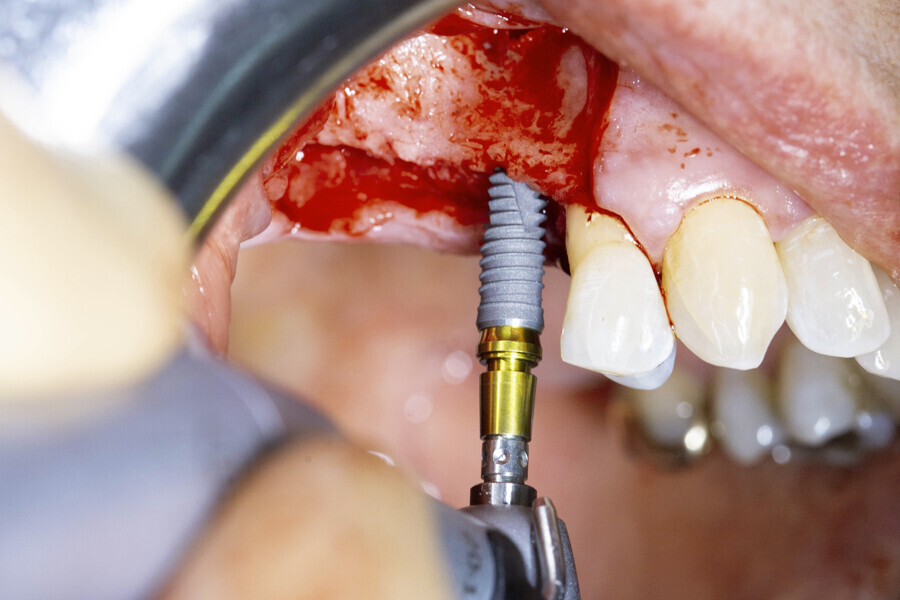

A full-thickness envelope flap was raised with relieving incisions, and the initial small round guide drill was used to mark the implant position. The site was enlarged with OmniTaper drills of different diameters, following the recommended drilling protocol. The initial osteotomy preparation was performed with a 2mm diameter OmniTaper drill at no more than 1,500 rpm and with copious external irrigation with saline according to the surgical protocol (Fig. 3). An OmniTaper EV 3.8 × 11.0 mm implant was placed in position #15 using the TempBase driver (Fig. 4). Both OmniTaper EV implants placed with the help of the preassembled TempBase abutments nicely aligned in positions #15 and 16 (Fig. 5).

Fig. 3: Full-thickness envelope ap and direction indicators after initial preparation with the 2 mm diameter OmniTaper drill.

Fig. 4: Placement of the OmniTaper EV implant in position #15 using the TempBase driver.